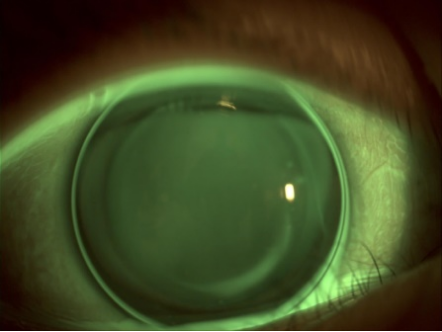

图2. 配镜1月复查时,右眼中央角膜上皮轻度损伤,无基质浸润

图4. 右眼原镜片荧光静态配适图(欧几里得 43.50/-4.50/11.0 AC42.75 T1.50)

镜片配适评估:右眼静态配适直径覆盖度好,呈中心定位,动态活动度佳,中央光学区镜片与角膜接触提示矢高偏低,水平方向定位区着陆理想,垂直方向定位区镜下泪液荧光逃逸。

新镜片角膜覆盖度好,呈中心定位,活动度佳,静态配适360度边翘可见,定位区着陆均匀无荧光逃逸,基弧区无蓝黑色表现提示镜片矢高理想。